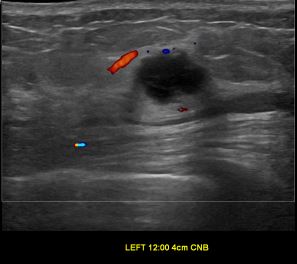

상기환자는 외부검사 이상소견으로 내원하신 50대중반 여성분으로 의심스러운 좌측혹

조직검사 시행해 유방암으로 진단되었습니다